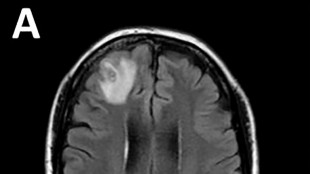

Cirujanos en EEUU realizan el primer trasplante de ojo completo del mundo

Un equipo de cirujanos de Nueva York informó el jueves que había realizado el primer trasplante del mundo de un ojo entero en un procedimiento descrito como un gran avance médico, aunque todavía no se sabe si el paciente recuperará realmente la vista.